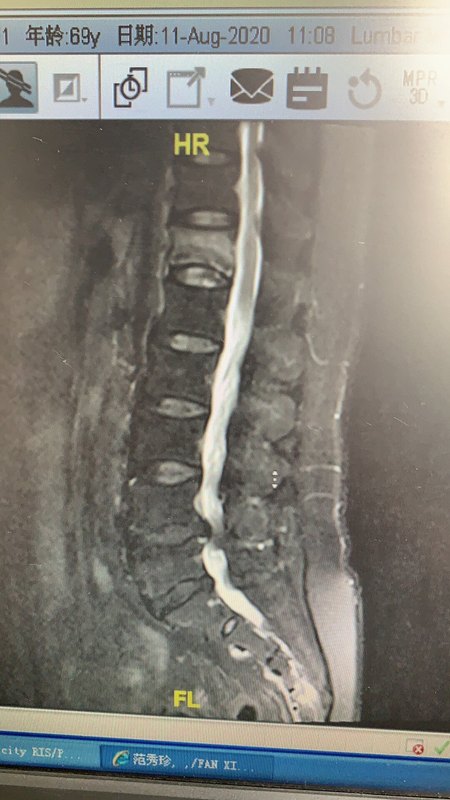

李大娘 年齡大了 不小心摔了屁股 卻感到腰疼難忍 本以為休息一下會好轉(zhuǎn) 可是越來越疼 晚上更疼 來到醫(yī)院一檢查 竟然是腰椎骨折了 李大娘不理解 其實是因為年齡大了 骨質(zhì)疏松了 摔一下就骨折 所以有的老年人就慢慢的駝背了 這可咋么辦 疼得受不了 不要著急 來醫(yī)院做個微創(chuàng)小手術(shù) 半小時后就不疼了 從背上穿兩個針 打上骨水泥讓骨折的椎體重新強壯起來 手術(shù)結(jié)束 第二天就出院了